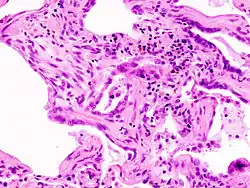

Modèle histologique d'une UIP. On voir les zones de fibrose dans les septums interalvéolaires. Coloration à l'hématoxyline-éosine (HE).

Le diagnostic se fait après enquête étiologique négative grâce à la combinaison de critères scanographiques et éventuellement anatomopathologies (après biopsie chirurgicale pulmonaire). L'aspect histologique typique est celui d'une UIP (de l'anglais « Usual Interstitial Pneumonia ») ou PIC en français (pneumonie interstitielle usuelle) qui se caractérise par une fibrose disséminée, des amas de fibroblastes, une distorsion architecturale marquée dans les régions septales et pleurales avec une structure en nid d'abeilles du poumon. Le modèle de l'UIP est caractéristique mais pas spécifique, et se présente dans d'autres variétés. Sur le scanner haute résolution, on parle aussi dans les formes typiques de tableau de PIC avec association de réticulations (dessins de réseaux et de lignes), d'élargissement des bronches par tractions, d'opacités floues dites en verre dépolien général peu étendues, d'aspect en nid d'abeilles dans les bases et les régions périphériques sous pleurales (destruction irréversible de l'architecture normale du poumon). Ces modifications sont le plus souvent bilatérales mais asymétriques et dans les bases des poumons.